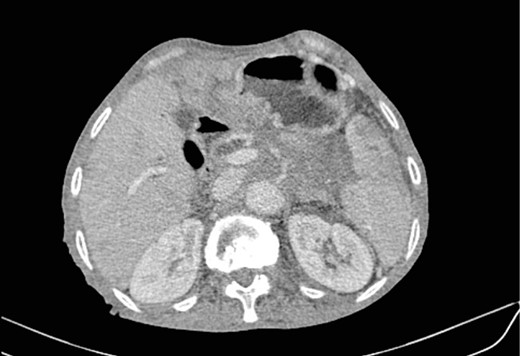

Mr. B. is a 59-year-old patient with no notable pathological history, presenting with melenas associated with marked weight loss. A fibroscopy revealed a thickened and ulcerated gastric mucosa. Abdominal and pelvic CT scans revealed a tissue process in the body and tail of the pancreas invading the splenic hilum, adjacent vessels ans gastric wall, measuring 11 cm long (Fig. 5). A caudal spleno-pancreatectomy enlarged to the colon, omentum and stomach was performed. Macroscopically, the tumor had a grayish–white appearance, poorly limited and indurated on palpation. Histologically, it was a well-differentiated, keratinizing squamous cell carcinoma of the tail of the pancreas (Figs 6 and 7), infiltrating the splenic hilum, gastric wall and colon.

HE section showing nests and sheets of polygonal cells surrounded by fibrotic desmoplastic stroma (x100).

HE section: Neoplastic cells have densely chromatic enlarged nuclei with prominent nucleoli. They are enlarged with abundant eosinophilic cytoplasm and focal keratinization. Intercellular bridges are slightly visible (x200).